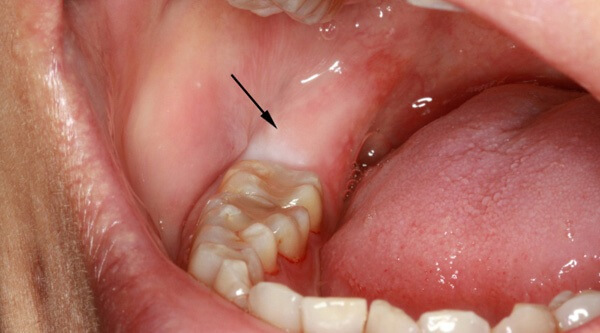

Неполное прорезывание приводит к формированию десневого капюшона – складки десны над зубом. Особенностью этого образования является то, что в него часто набивается пища, которую очень сложно вычистить зубной щеткой.

При обсеменении остатков пищи микроорганизмами развивается очень неприятное заболевание – перикоронарит.

- Иногда прорезывающийся зуб накрывает своеобразный «капюшон» из разросшейся слизистой. Под ним скапливаются остатки пищи и размножаются бактерии.

Этот процесс приводит не только к болезненности и отеку. Появляется неприятный запах изо рта и затруднение при глотании.

Признаки, связанные с воспалением десен

После еды там скапливаются остатки пищи, а при обычных гигиенических процедурах удалить их оттуда очень сложно. Поэтому в этом кармане развиваются бактерии, вызывающие воспалительный процесс.

У некоторых людей он протекает почти безболезненно и проходит сам. Но довольно часто появляются различные осложнения. Во время жевания десна может повредиться, бактерии проникают в ранку, и воспаление переходит в перикоронарит.

- Вздутие десны в виде «капюшона» над еще непрорезавшимся зубом. Если процесс роста затягивается, развивается воспаление мягких тканей после проникновения бактерий под «капюшон».